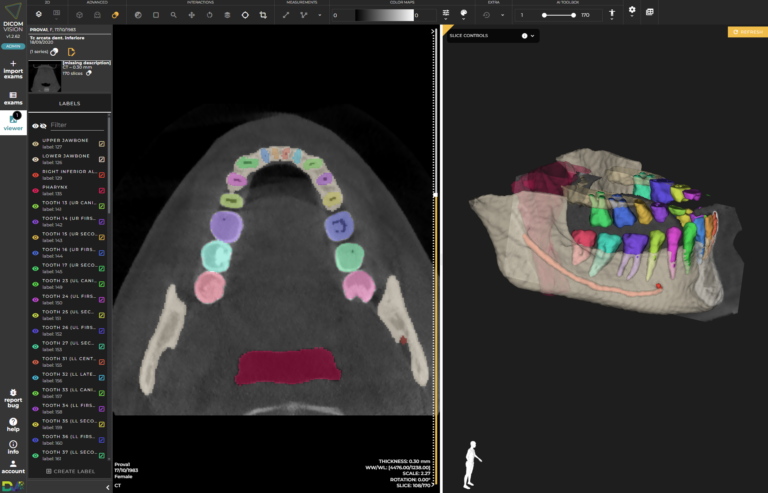

Una delle sfide più significative nella pratica medica contemporanea è la capacità di condividere rapidamente e in modo sicuro informazioni critiche tra specialisti. DICOM Vision affronta questa sfida testa a testa, offrendo una piattaforma dove i professionisti possono condividere casi per una “second opinion”, collaborare in tempo reale su diagnosi complesse, e molto altro ancora. Grazie alla possibilità di prendere misure e annotazioni direttamente sulle immagini condivise, i team medici possono lavorare insieme come se fossero nella stessa stanza, nonostante le distanze geografiche che li separano.

Radiologia: DICOM Vision è particolarmente adatto per le pratiche radiologiche, consentendo ai radiologi di visualizzare e analizzare immagini mediche come raggi X, scansione CT e MRI con facilità. Le sue caratteristiche avanzate, come la visualizzazione 3D e l’integrazione dell’IA, migliorano le capacità diagnostiche.

Pianificazione Chirurgica: I chirurghi possono utilizzare DICOM Vision per pianificare le operazioni in modo più efficace visualizzando strutture anatomiche e patologie specifiche del paziente in 2D e 3D. Ciò aiuta nella valutazione preoperatoria e nella strategia.

Ricerca Clinica: I ricercatori medici possono utilizzare DICOM Vision per accedere e analizzare grandi insiemi di dati di imaging medico. Le capacità dell’IA assistono nell’automatizzazione di determinati compiti, mentre la visualizzazione 3D può aiutare a comprendere relazioni anatomiche complesse.